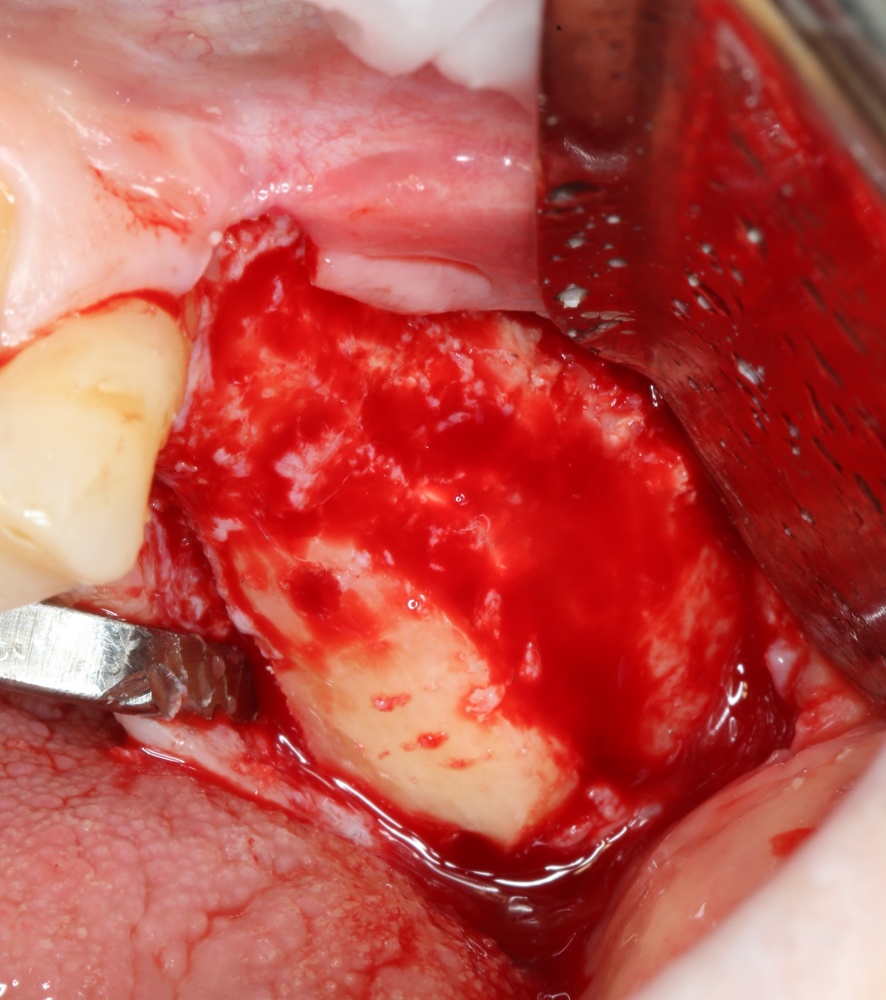

Кстати, обрати внимание на ширину альвеолярного гребня (левая картинка). Она чуть меньше 3 мм. Это объясняет, почему я засомневался в возможности установки имплантатов одновременно с остеопластикой. Понятно и без КЛКТ.

Наперво, мне нужно удалить разрушенный зуб и получить костный аутотрансплантат.

Для получения костного блока, мы открываем донорскую зону, наружную косую линию нижней челюсти.

Получение костного аутотрансплантата.

Здесь потребуется пародонтологический зонд с миллиметровой разметкой или какой-то другой измерительный прибор (операционная линейка). Ранее по КЛКТ я измерил костный дефект, теперь нужно нанести границы будущего костного блока на донорскую зону.

Для получения костного блока мы использовали ультразвуковую пьезохирургическую систему. Это самый удобный и безопасный инструмент для проведения подобных манипуляций. С помощью него мы сформировали и выделили костный блок. Он должен отделяться легким движением остеотома или элеватора. Как это сделать правильно — читай здесь>>

Подготовка костного ложа и фиксация аутотрансплантата

Возвращаемся к основной операционной области. Еще раз посмотрим на альвеолярный гребень, поофигеваем от его ширины и моих грандиозных планов: